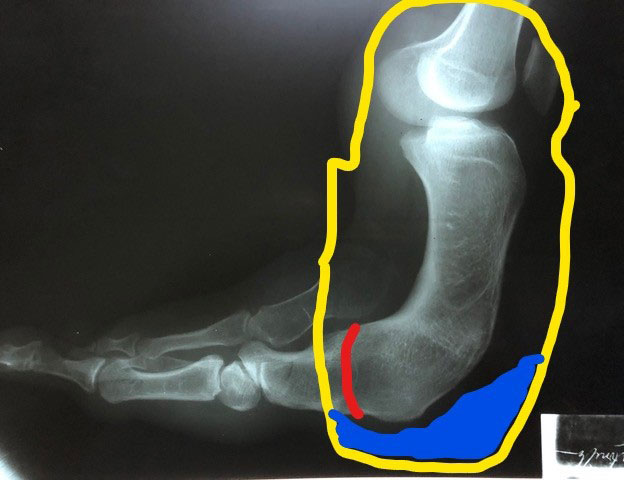

The surgeons, in consultation with the prosthetist, decided that it would be best to amputate Levin’s dysfunctional foot at the point indicated by the red line in this picture of the X-Ray. ROMP-Guatemala would then fabricate the prosthetic socket represented by the yellow lines.